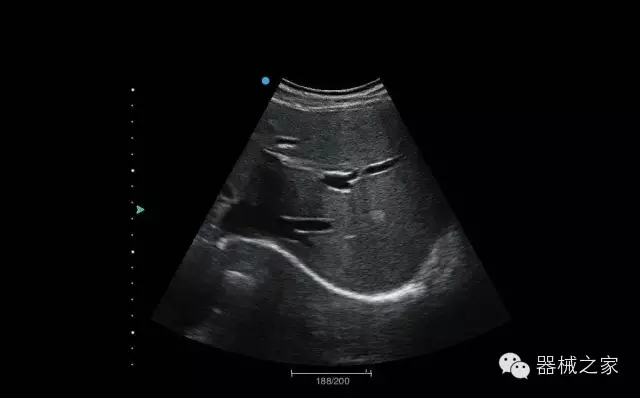

經(jīng)典產(chǎn)品:Apogee 1000

臨床圖片賞析

結(jié)甲

腎臟血流

肝血管瘤

產(chǎn)品特點

·屏幕可左右90度旋轉(zhuǎn);

·雙模操控;

·兩用提手;

·雙鋰電池;

·超輕機身;

·15寸高亮高清醫(yī)學(xué)顯示器;

·衛(wèi)星布局操控面板;

·一體化剪切板;

·多功能導(dǎo)航鍵;

“宏云”平臺

·采用移植自高端臺式彩超的“宏云”平臺技術(shù),使系統(tǒng)具有更優(yōu)秀的圖像效果;

人性化的設(shè)計

·內(nèi)置電池,輕巧的外觀設(shè)計以及臨床功能、軟硬件設(shè)計的人性化設(shè)計,使系統(tǒng)在臨床多科室移動診查中,均從容應(yīng)對;

Fusion THI二代融合諧波成像

·在不同諧波頻率段獲得的信息進(jìn)行實時融合,既能獲得諧波圖像分辨率又能提高圖像的穿透力,降低圖像噪音;

XBeam多域復(fù)合成像

·通過頻域和空域角度進(jìn)行復(fù)合的圖像處理,能有效消除由于圖像離散化和圖像衰減引起的空間分辨率下降的不利影響,彌補原有圖像空間分辨率的不足,獲得更加清晰的圖像;